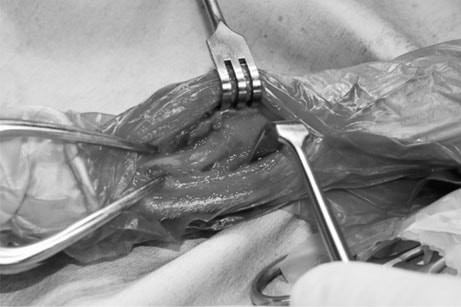

脊髄の減圧、脊柱管の再構築・安定化を目的に、片側椎弓切除術およびMatrixMANDIBLE Plateによる椎体固定を実施しました。

隣接椎体を架橋するようにプレートを設置しました。

Arthrex社のターゲティングデバイスを用いてピンニングの位置を調整することで、確実な固定を行っています。当院ではこの手術器具以外にも、人の手術にも使用される様々な器具を導入し、手術精度を高め、また医療メーカーと新しい器具の開発、試作にも取り組んでおります。